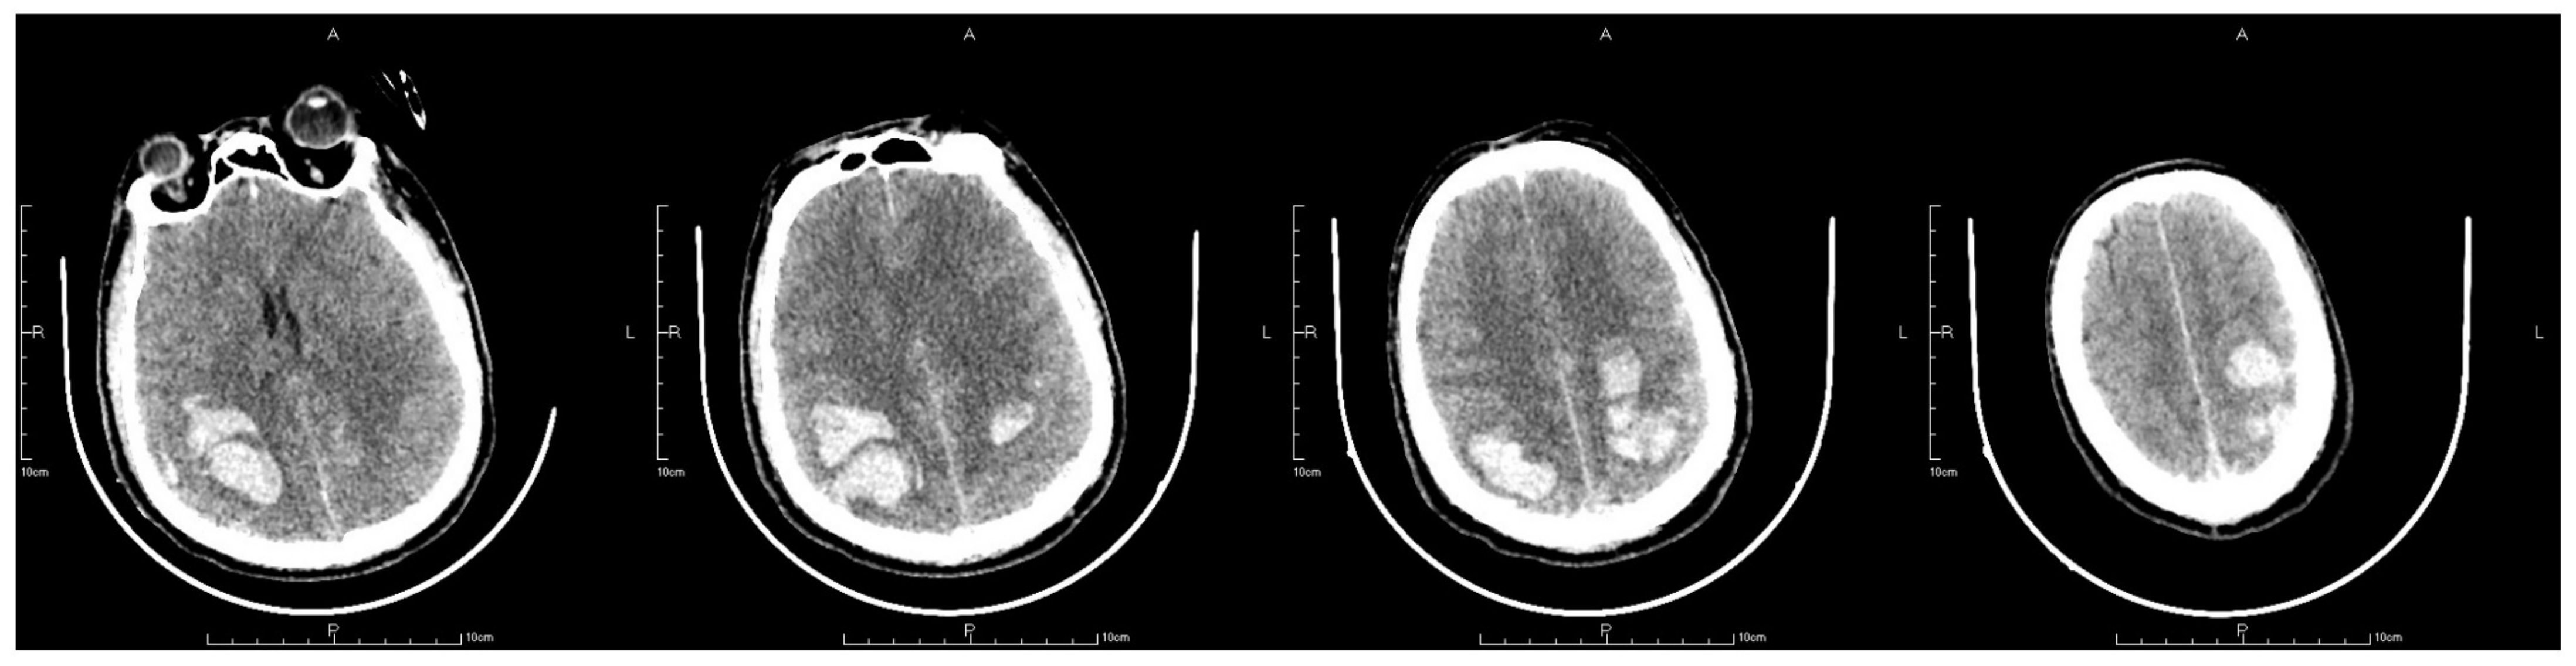

After the surgery, routine postoperative management was employed. Mask inhalation was applied constantly with a flow rate of 5 L/min; 250 mL mannitol was used to reduce the intracranial pressure; 8 mg noradrenaline was constantly pumped in to maintain blood pressure within a normal range; and 50 μg sufentanil was also pumped in for sedation and pain relief. However, 2 h after the surgery, the patient suddenly presented with vomiting and idiopathic myosis with a diameter of only 1.5 mm, and did not react to light. An emergency CT scan revealing a postoperative change after the thrombectomy was obtained. The CT scan showed expanded hemorrhagic areas along with bilateral intraparenchymal hematomas in the frontoparietal lobes (Figure 5). Concurrently, the emergency arterial blood gas revealed the following: pH, 7.296; PCO2, 32.6 mmHg; PO2, 63.5 mmHg; and cHCO3, 15.5 mmol/L. Emergency tracheal intubation with an invasive ventilator was implemented to ensure that the airway was unobstructed. Mannitol was applied again to enhance intracranial pressure reduction. Another cerebral CT scan was also obtained on the first postoperative day, which demonstrated that the hemorrhagic areas on the right frontoparietal lobes and epencephalon had further expanded (Figure 6). On the second postoperative day, the patient’s autonomous respiration and heartbeat ceased concomitantly with corectasis. The emergency electrocardiogram depicted an equipotential line, following which the patient was pronounced dead.

Figure 5.

The letter R, A, P, L in the figures refers to Right, Anterior, Posterior and Left, respectively. CT scan after thrombectomy showed postoperative changing with expanded hemorrhage areas in bilateral frontoparietal lobes together with bilateral intraparenchymal hematoma in the frontoparietal lobes.

Figure 6.

The letter R, A, P, L in the figures refers to Right, Anterior, Posterior and Left, respectively. Last CT before death showed hemorrhage areas on right frontoparietal lobes and further expansion of epencephalon.